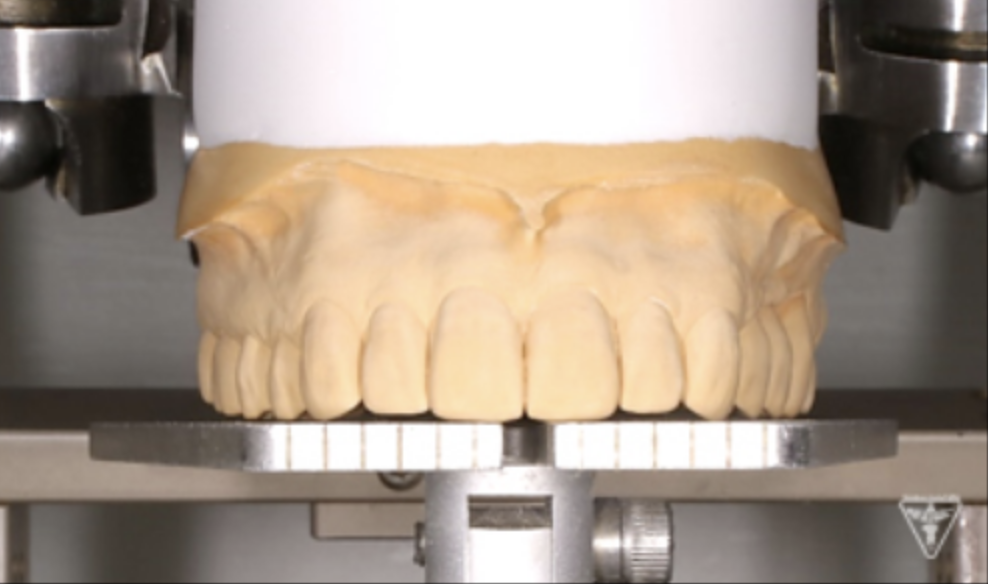

サージカルガイドの作成

最終補綴物装着時